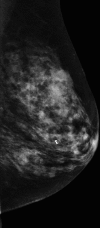

Paraneoplastic polymyositis presenting as a clinically occult breast cancer

Paraneoplastic syndrome affects less than 1% of cancer patients. Diagnosis of paraneoplastic syndrome with neurological presentation requires screening for an underlying malignancy, including a complete history, physical examination and imaging studies. Treatment often results in symptom stability, rather than improvement. Paraneoplastic polymyositis can precede or instantaneously occur at diagnosis or treatment of a primary tumour, while neurological symptoms can persist even following cancer treatment. We report a rare case of metaplastic breast carcinoma with an unusual presentation of paraneoplastic polymyositis.